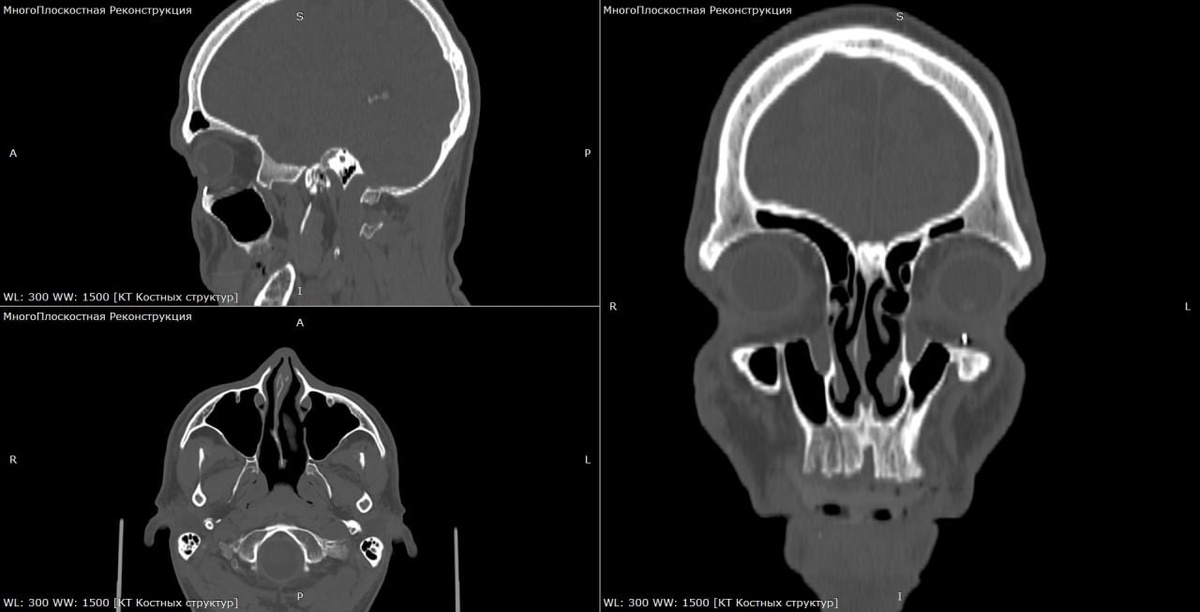

Боец СВО год прожил со снайперской пулей в глазу.

45-летний военный обратился в больницу Жуковского с жалобами на боль. Выяснилось, что год назад мужчине в лицо попала пуля, которая мигрировала. Врачи два часа оперировали пациента, чтобы убрать металлический осколок из глаза и сохранить зрение.

К счастью, боец уже восстановился и в ближайшее время планирует продолжить службу.